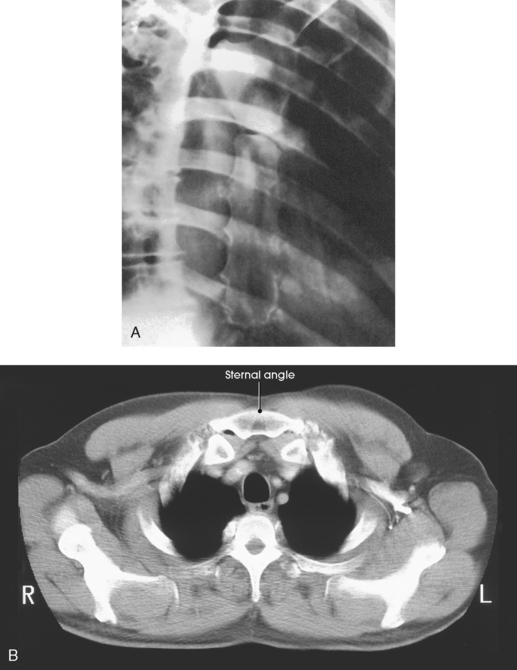

Angulation of the body or the central ray to project the sternum to the right of the thoracic vertebrae clears the sternum of the vertebrae but superimposes it over the posterior ribs and the lung markings (Fig. 9-11). If the sternum is projected to the left of the thoracic vertebrae, it is also projected over the heart and other mediastinal structures (Fig. 9-12). The super imposition of the homogeneous density of the heart can be used to advantage (compare Figs. 9-11 and 9-12).

The pulmonary structures, particularly in elderly persons and heavy smokers, can cast confusing markings over the sternum, unless the motion of shallow breathing is used to eliminate them. If motion is desired, the exposure time should be long enough to cover several phases of shallow respiration (Figs. 9-13 and 9-14). The milliampere (mA) must be relatively low to achieve the desired milliampere-second (mAs).